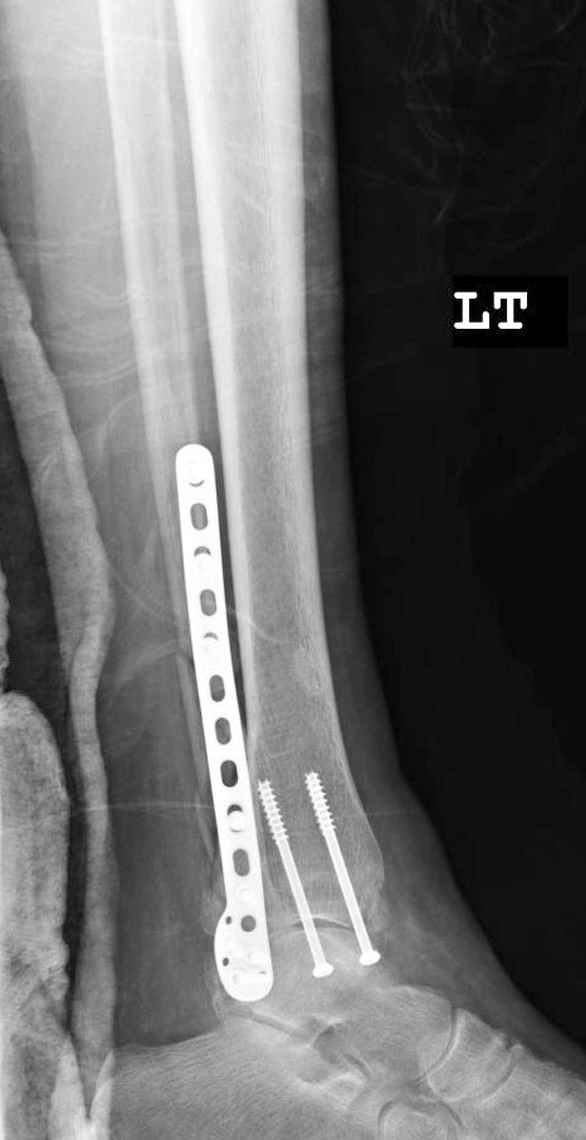

Здесь финальный снимок 73 летней с

сопутствующей шизофренией, латерально бридж

пластину (соединили дистальный конец с диафизом не трогая место перелома) и медиально перкутанно

двумя шурупами. В этам случае без гипса не

обойтись.

Точно, для идеальной репозиции надо открыть передний и задний углы медиальной лодыжки,

сделать ревизию сустава, очистить, убрать интерпозицию, потом только зафиксировать.

Как заметил, по рентгенограмме медиальная лодыжка не очень идеально репонирована. Больная кроме шизофрении страдала другими соматическими заболеваниями, и во время операции от анестезиолога получил рекомендацию поторопиться, поэтому решили закрыто, а так тенденция лечить

открытым методом.